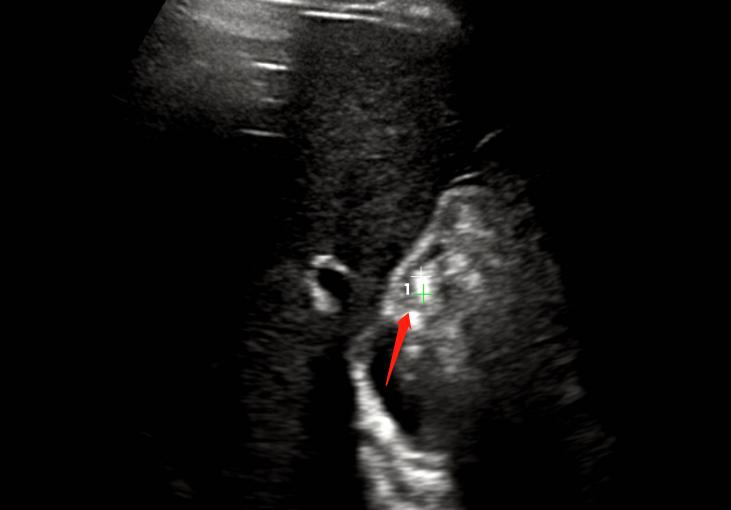

胆囊如图:

两年前的胆囊

从上图来看,胆囊内确实没有明显异常,只是形态看起来有些饱满,但胆囊颈部未能完全显示,肝外胆管也未能显示清楚。